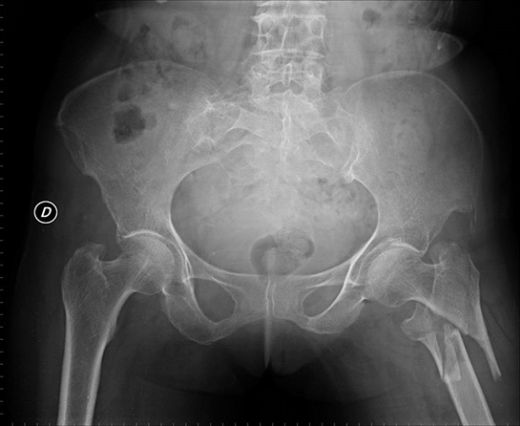

Ayak bileği çatlakları, genellikle spor yaralanmaları, düşme veya aşırı zorlanma gibi durumlar sonucunda meydana gelir. Bu tür yaralanmalar, ağrı, şişlik ve hareket kısıtlılığına yol açabilir. Ayak bileği çatlaklarının tedavisi, yaralanmanın ciddiyetine ve türüne bağlı olarak değişiklik göstermektedir. Bu makalede, ayak bileği çatlaklarının tedavi yöntemlerini detaylı bir şekilde ele alacağız.

Ayak bileği çatlağı, ayak bileğindeki kemiklerin (genellikle tibia, fibula veya tarsal kemikler) bütünlüğünün bozulmasıyla oluşan bir yaralanmadır. Bu tür yaralanmalar, çeşitli derecelerde olabilir ve genellikle aşağıdaki belirtilerle kendini gösterir: